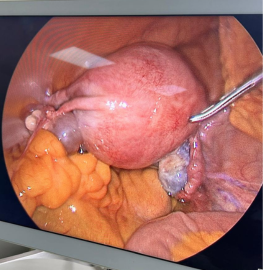

42 Year Old Female with 25cm Ovarian Cyst